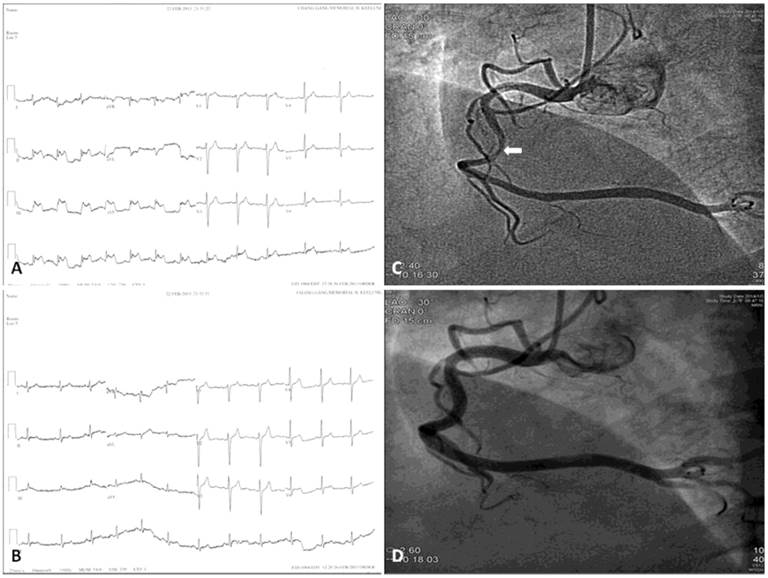

Electrocardiographic measurements may appear normal at the beginning of CAS or when the CAS is mild [27]. Total or subtotal spasm of a major coronary artery results in ST-segment elevation in the leads corresponding to the distribution of that coronary artery. However, CAS may cause ST-segment depression, indicating less severe, subendocardial myocardial ischemia than does ST-segment elevation. Of note, CAS is more frequently associated with ST-segment depression (Figure 1) rather than ST-segment elevation (Figure 2) [10,11]. ST-segment depression occurs when CAS of a major artery is less severe, when a major artery receiving collaterals is completely occluded, or when a small artery is completely occluded [30]. This situation occurs in many cases of unstable angina/non-ST-elevation myocardial infarction. A previous study has shown that 45% of patients with angina at rest and ST-segment depression alone had CAS [15]. In addition to ST-segment changes, a delay in the peak and an increase in the height and width of R wave, a decrease in magnitude of S wave, peak T wave and negative U wave may also appear [27].

Figure 1

(A) Twelve-lead electrocardiogram in a 50-year-old male showing T-wave inversion in leads I, aVL, V2-6. (B) Normal electrocardiogram after 6-month treatment with diltiazem. (C) More than 90% spontaneous vasospasm in the proximal left anterior descending artery (arrows). (D) The vasospasm was relieved after intracoronary administration of 100-μg nitroglycerin (arrows). (Reproduced from Hung MY, Hsu KH, Hung MJ, Cheng CW, Kuo LT, Cherng WJ. Interaction between cigarette smoking and high-sensitivity C-reactive protein in the development of coronary vasospasm in patients without hemodynamically significant coronary artery disease. Am J Med Sci. 2009; 338(6): 440-446, with permission of the publisher. Copyright © Wolters Kluwer Health, 2009.)

Treatment